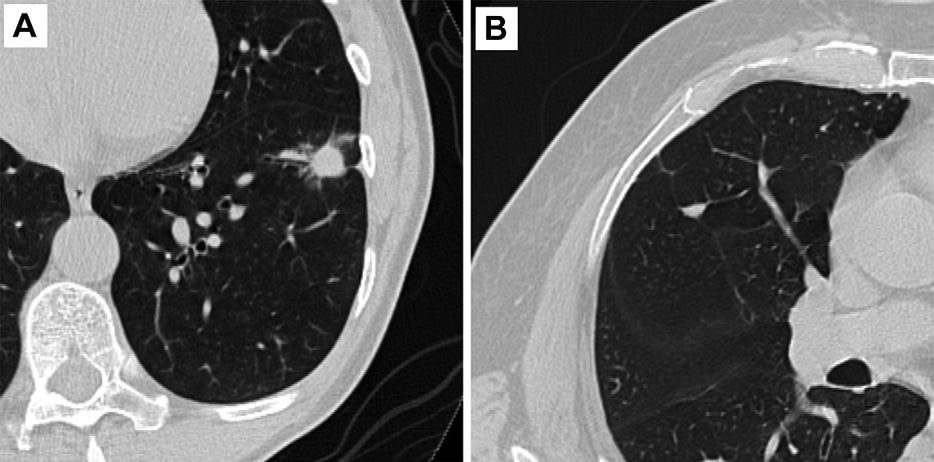

In a recent video interview, two radiology professors from the Yale School of Medicine discussed the impact of the iodinated contrast media (ICM) shortage and potential strategies, ranging from ICM dose reduction to possible deferment of non-urgent imaging, that may provide a viable path moving forward.